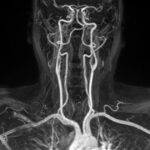

MR Angiography Neck